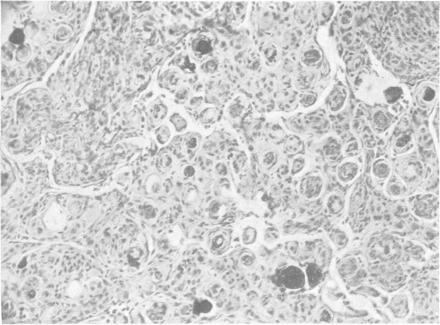

Intra-orbital meningioma of the optic nerve.

Br J Ophthalmol. 1953 Aug;37(8):506-7. doi: 10.1136/bjo.37.8.506.